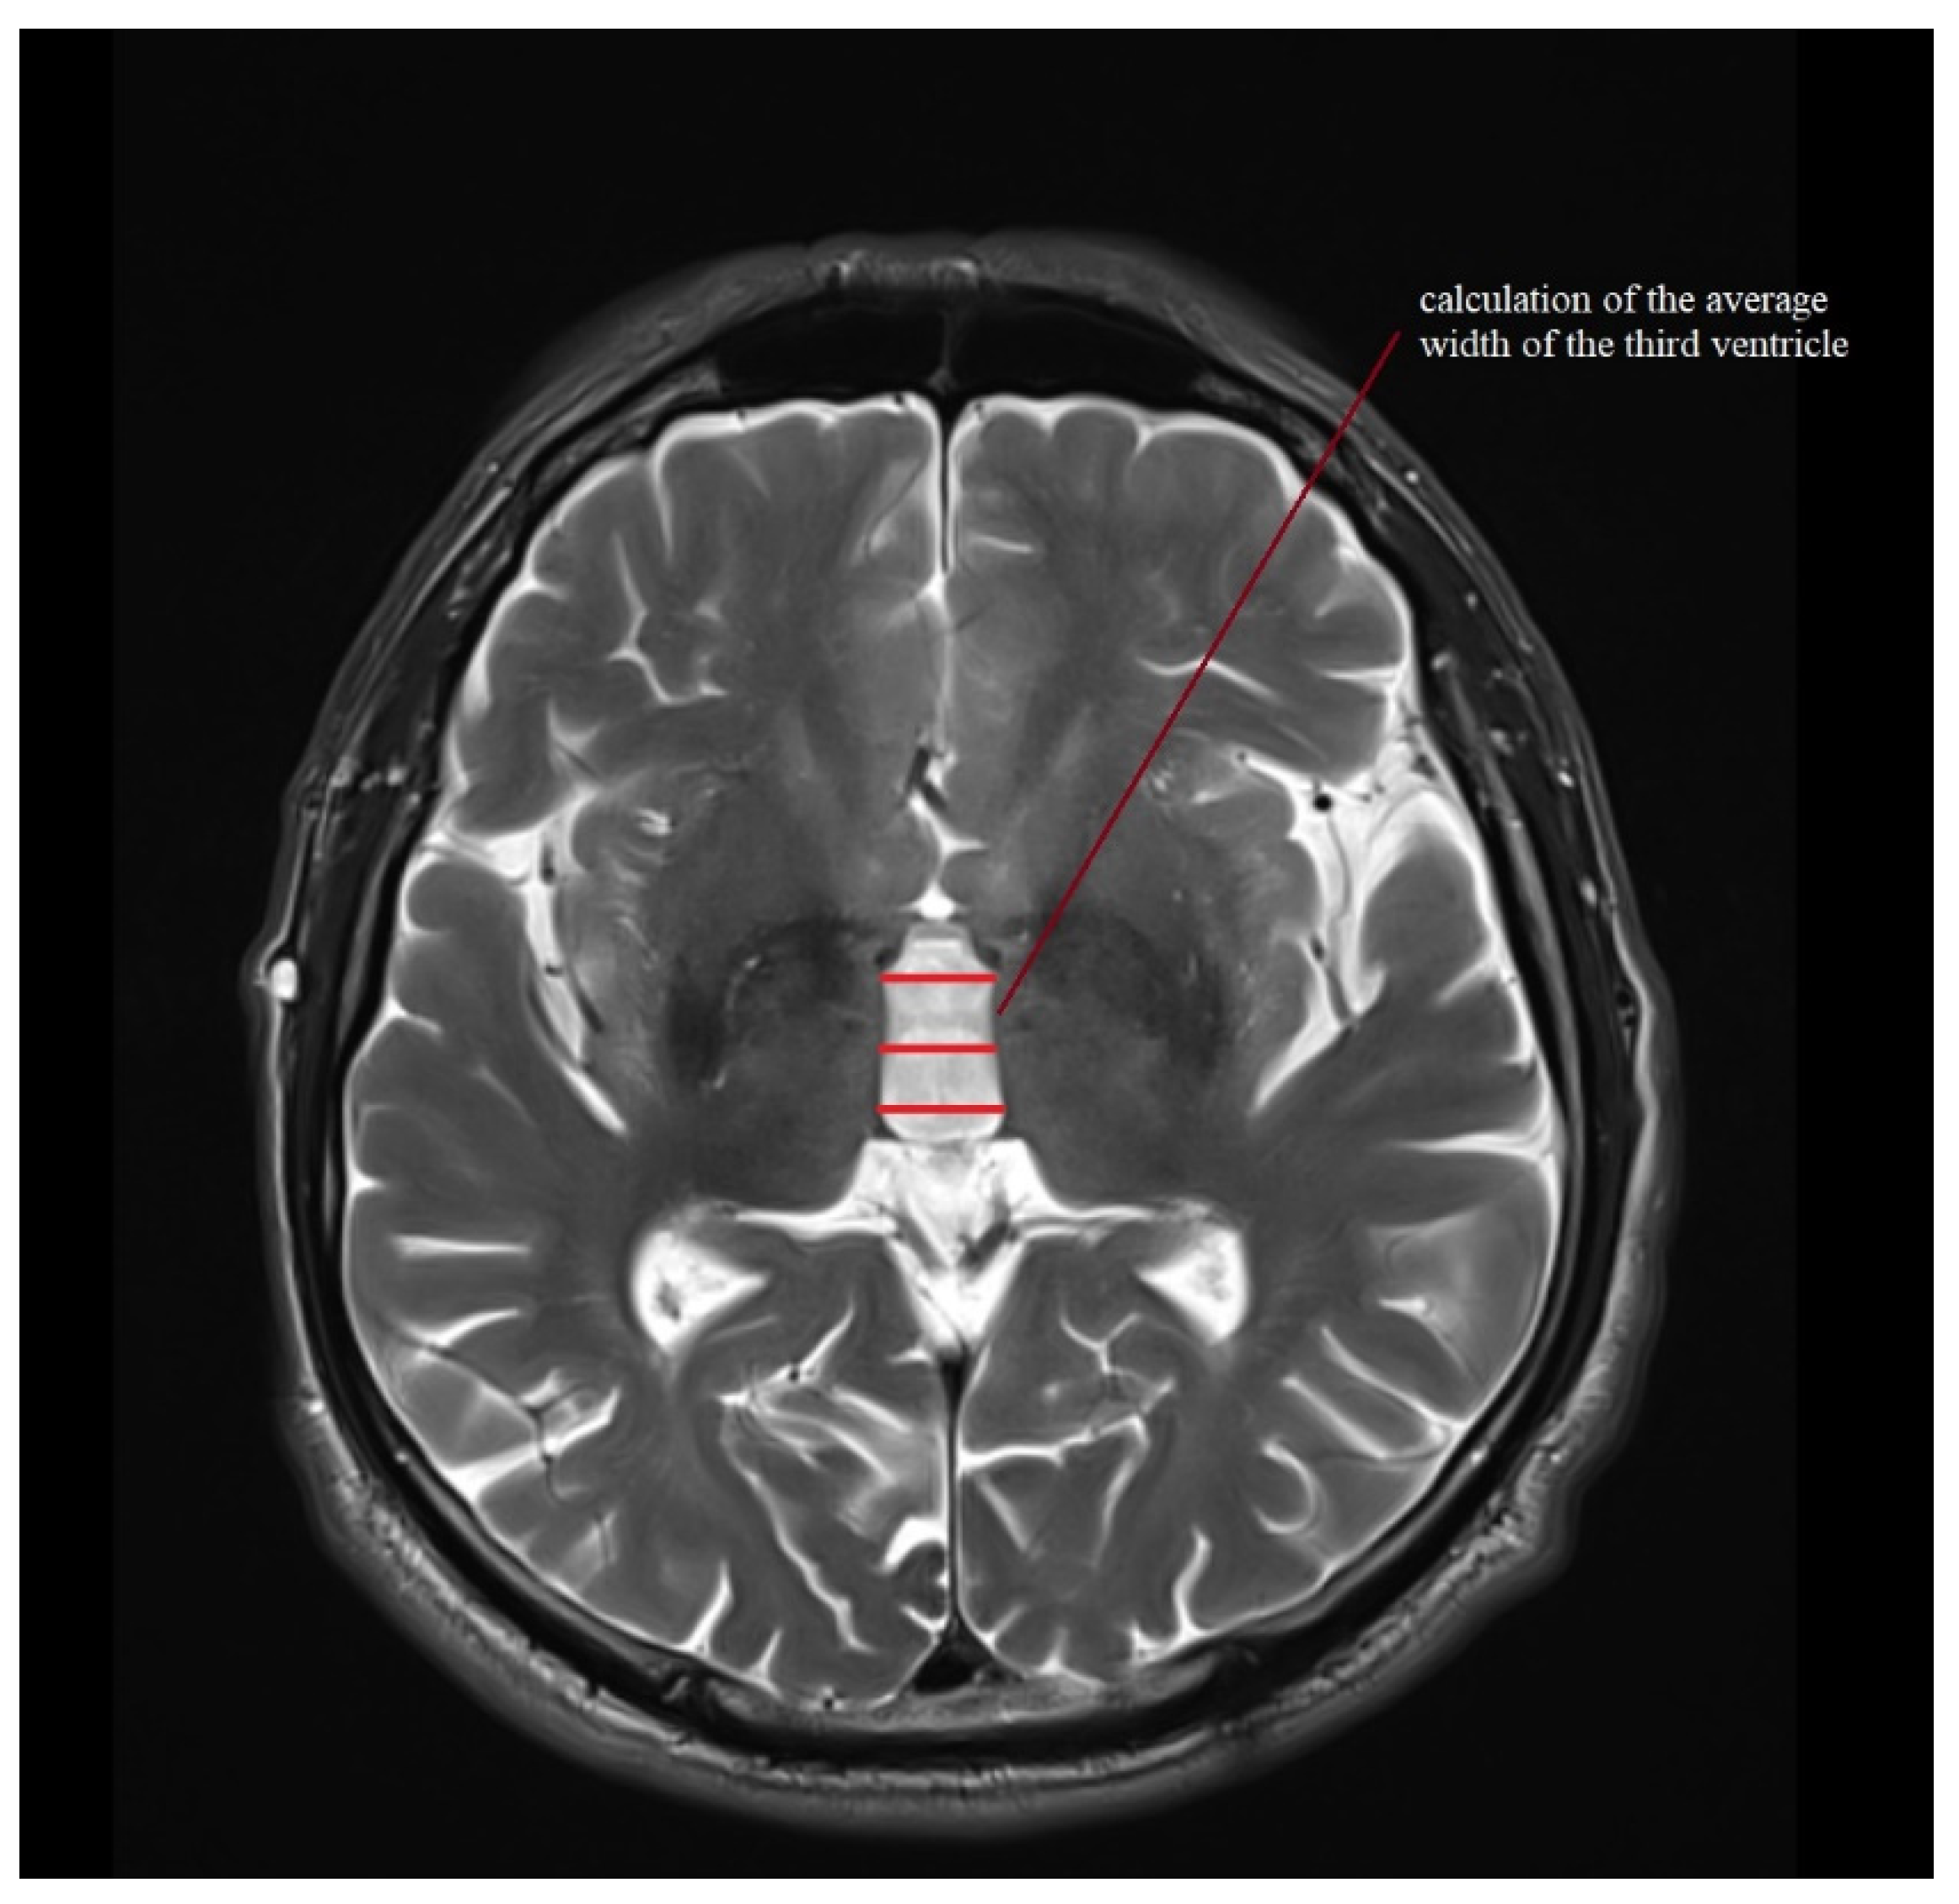

| III ventricle (mm) | 7.6 (4.2–12.5) | 2.2 ± 1.6–3.4 | 11.1 (6–16) | 2.5 ± 1.8–4 | 12.2 (5–19) | 3.1 ± 2.4–4.6 | 9.4 (6–14) | 2.5 ± 1.9–3.6 | 10.3 (7–14) | 2.1 ± 1.6–3.1 |

| MRPI | 11.247 (7.758–15.429) | 1.882 ± 1.39–2.912 | 17.384 (12.025–26.626) | 4.439 ± 3.183–7.327 | 19.366 (9.343–31.303) | 6.944 ± 5.247–10.27 | 10.766 (7.163–17.151) | 2.503 ± 1.915–3.614 | 15.363 (6.582–29.025) | 5.03 ± 3.801–7.439 |

| MRPI 2.0 | 2.342 (1.252–3.463) | 0.619 ± 0.457–0.958 | 4.338 (2.526–6.306) | 1.344 ± 0.964–2.219 | 5.646 (2.595–9.838) | 2.324 ± 1.756–3.436 | 2.558 (1.41–4.549) | 0.91 ± 0.696–1.314 | 4.195 (1.953–9.285) | 1.686 ± 1.274–2.493 |